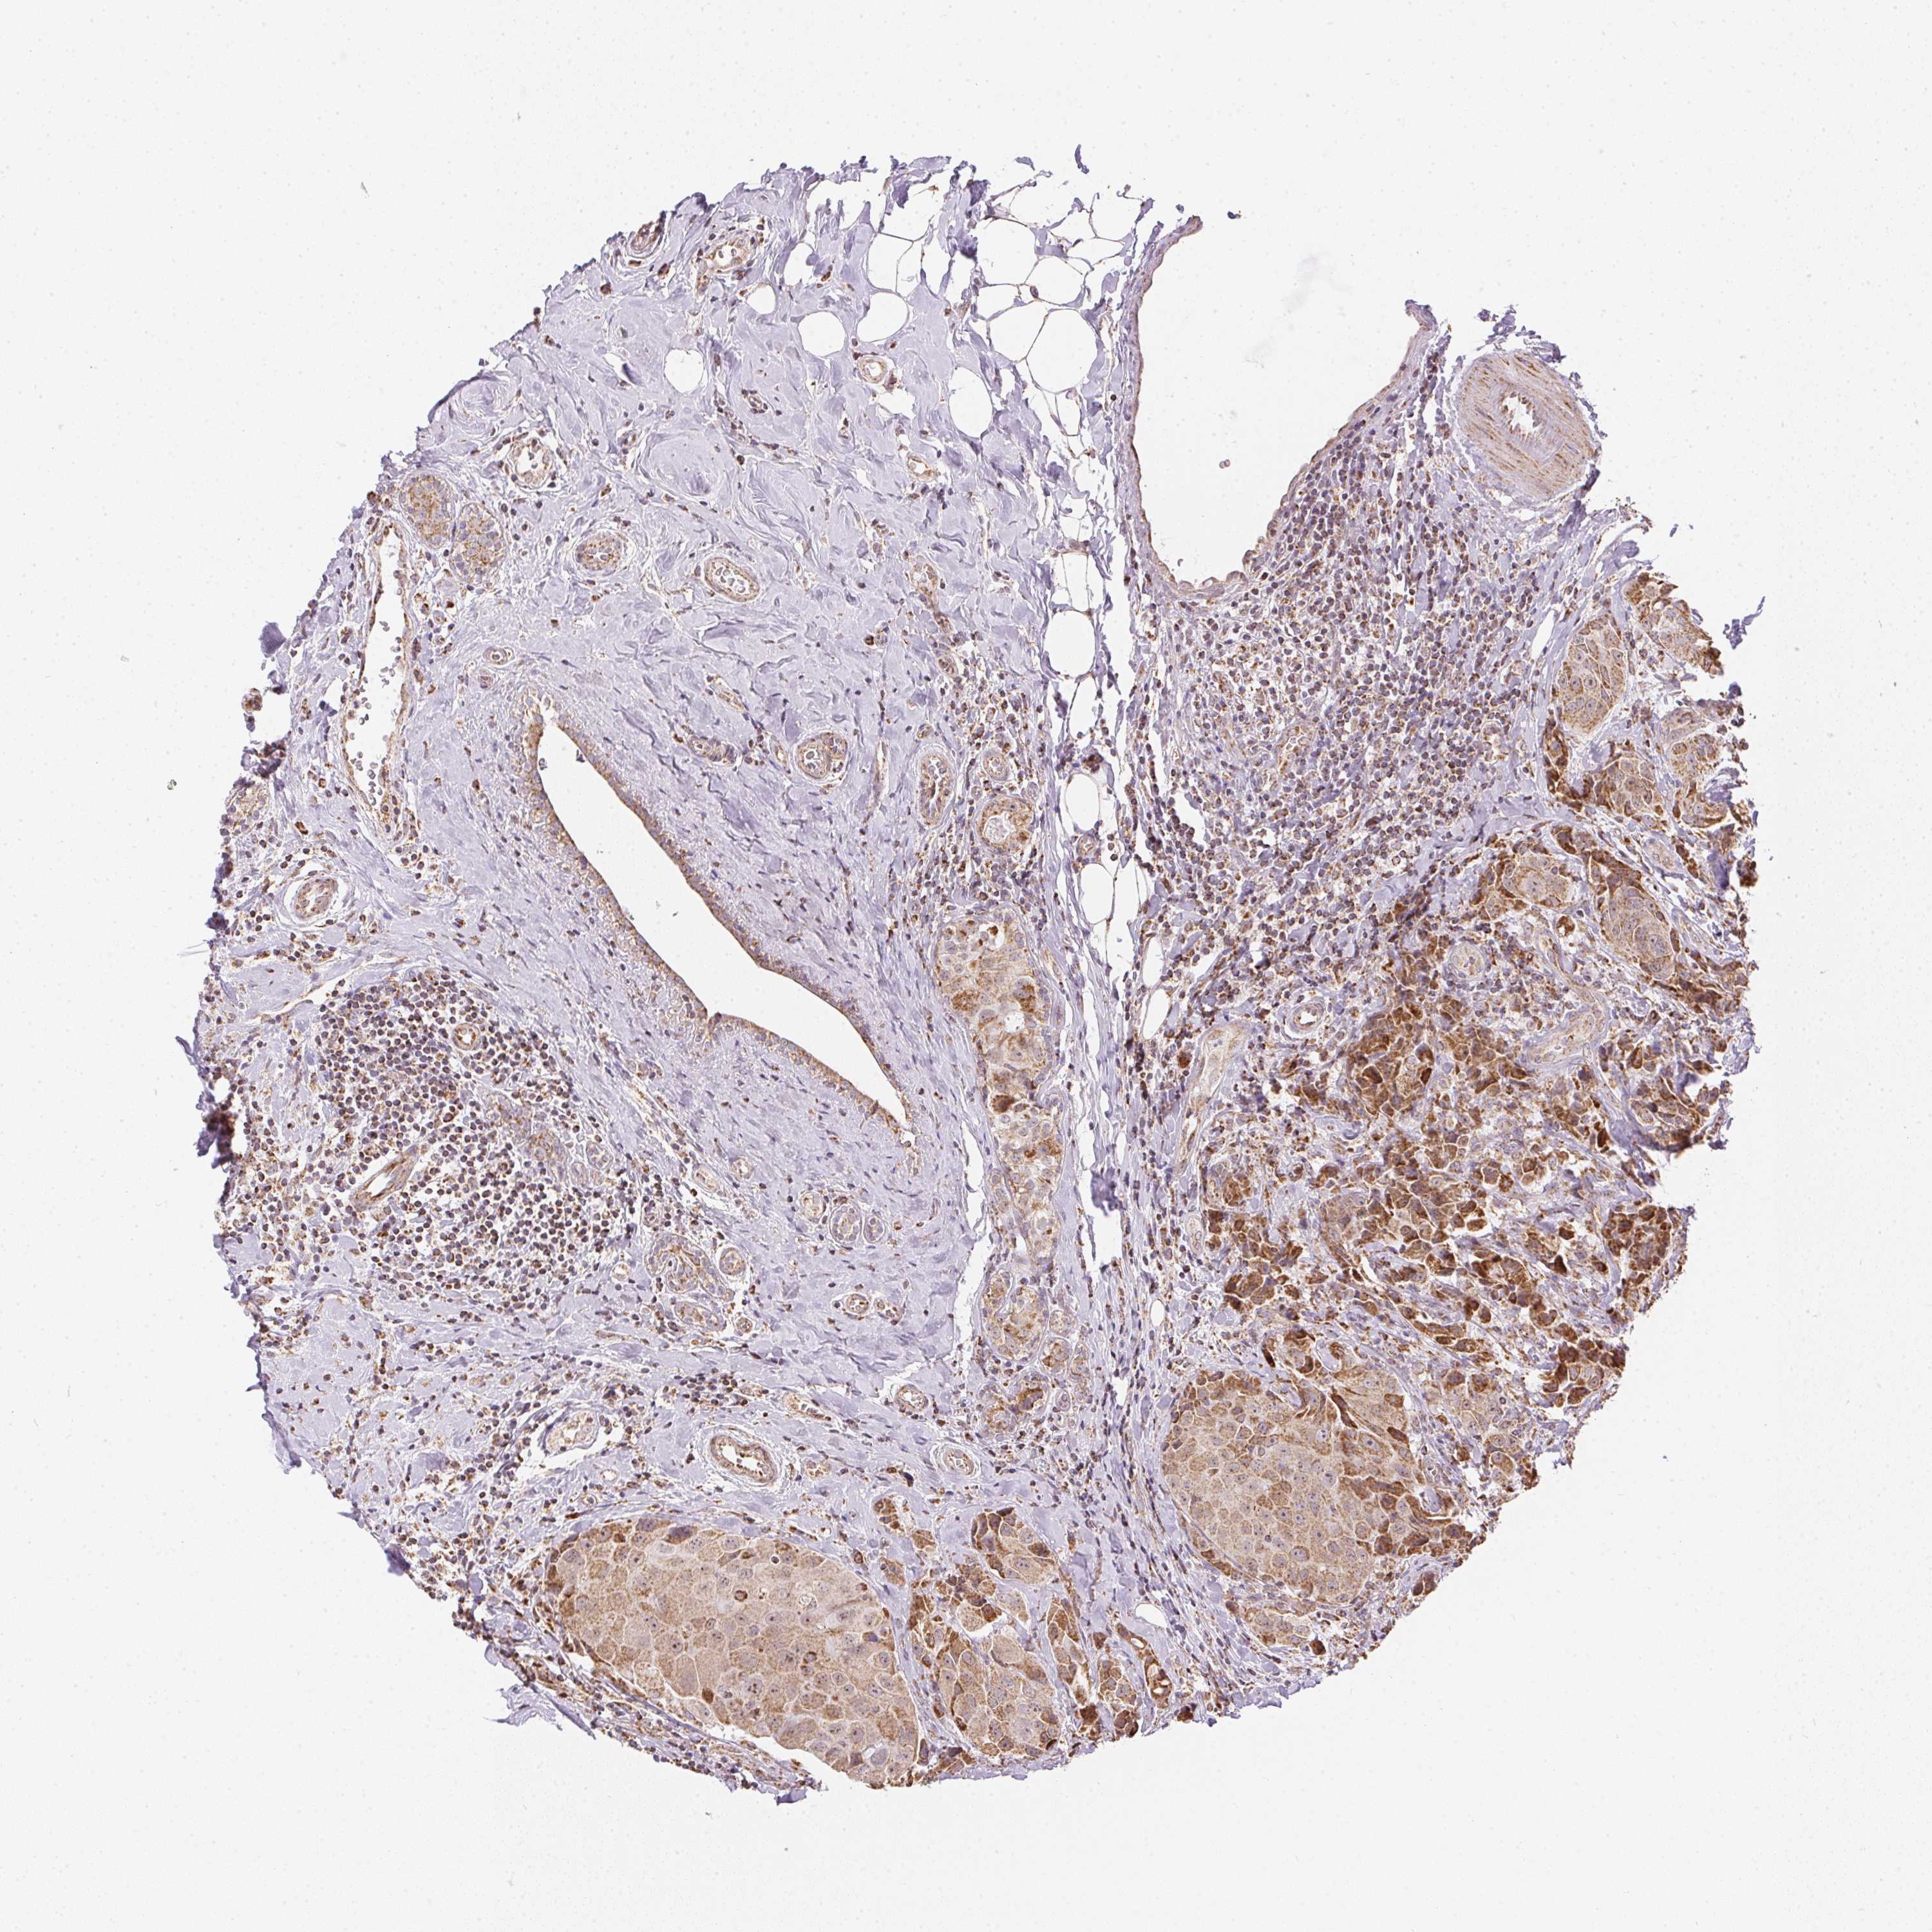

CANCER BREAST CANCER Show tissue menu

BRCA TCGA BRCA VALIDATION PROTEIN EXPRESSION

ANTIBODIES

AND

VALIDATION